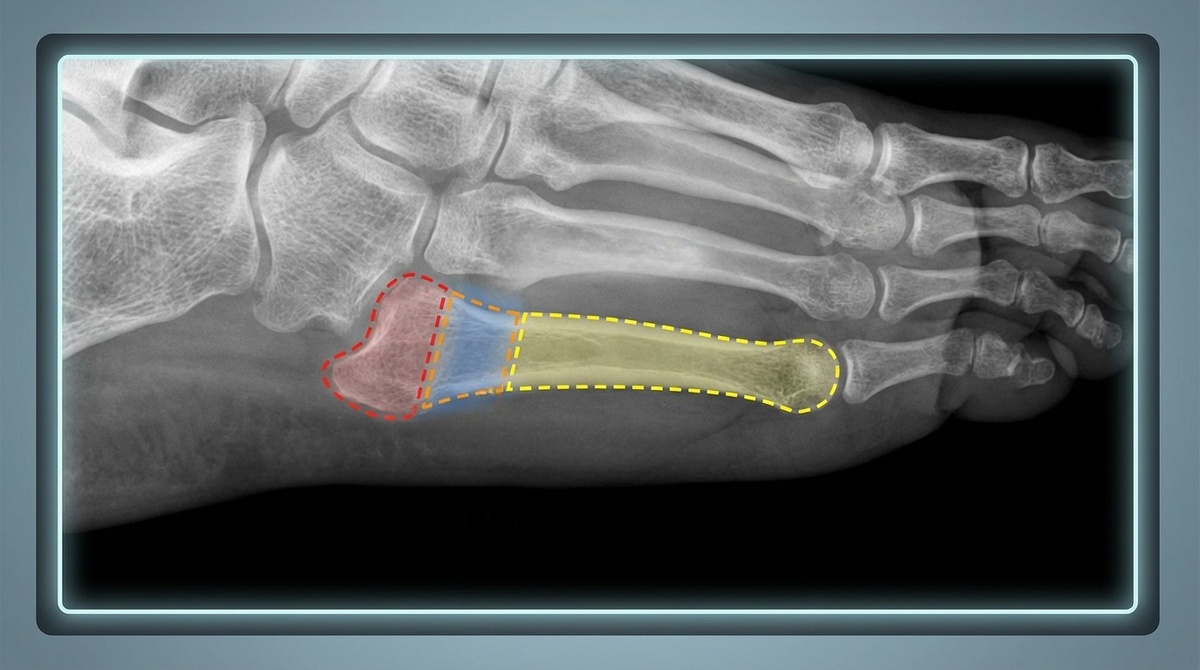

У основания 5-й плюсневой условно выделяют три зоны:

• Зона 1: отрывной перелом бугристости (обычно заживает легче).

• Зона 2: перелом Джонса, переход между основанием и телом кости.

• Зона 3: ближе к диафизу, нередко стресс-переломы.

Почему столько внимания к зоне 2?

Потому что это сосудистое «пограничье» — крови здесь меньше, а значит, кость срастается более капризно и медленно.